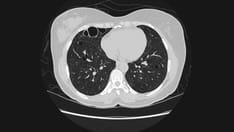

This chest CT scan was obtained on the same day as the chest radiograph of the patient in Media File 4. The image shows a loculated pneumothorax in the mid left lung. This image illustrates the information a chest CT scan can add and the difficulty in diagnosing a pneumothorax with the limited views provided by a portable chest radiograph.